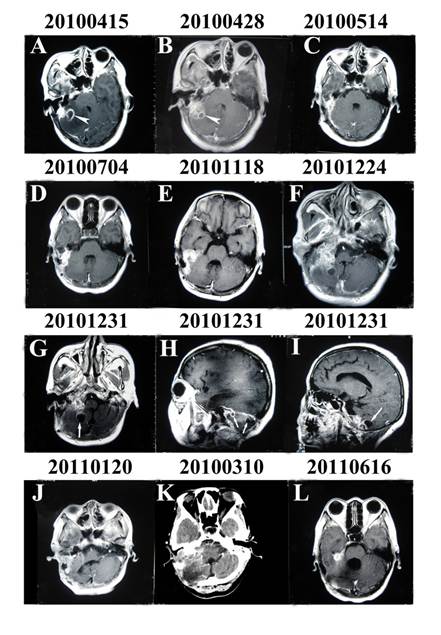

Figure 1

Enhanced MRI and CT of the brain through the entire course of the illness. (A) and (B) Enhanced MRI showing a ring-enhancing lesion in the right cerebellum suggesting an otogenic pyogenic abscess (arrowhead). (G), (H) and (I) Enhanced MRI showing multiple oval-shaped contrast-enhanced lesions (arrow) with irregular thick peripheral enhancement which were hypointense in T1-weighted images and hyperintense in T2-weighted images and which occupied the right cerebellum.